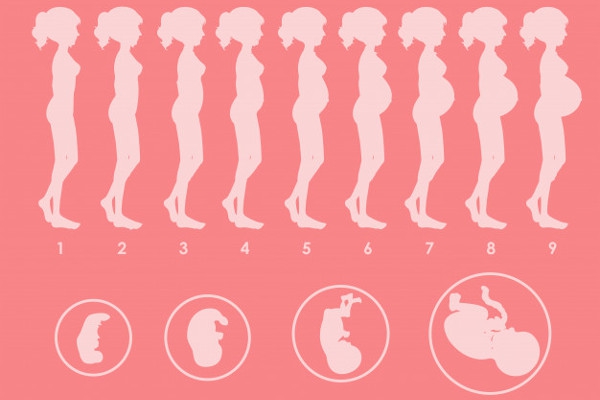

Bunda Inilah Berbagai Perubahan Pada Kehamilan Minggu Ke 7

Bunda Inilah Berbagai Perubahan Pada Kehamilan Minggu Ke 7

Minggu Kehamilan 7 Gejala Saiz Bayi Perubahan Badan Banyak Lagi Kehamilan 2021

Minggu Kehamilan 7 Gejala Saiz Bayi Perubahan Badan Banyak Lagi Kehamilan 2021

Perkembangan Janin 7 Minggu Kehamilan Perubahan Ibu Bayi

Perkembangan Janin 7 Minggu Kehamilan Perubahan Ibu Bayi